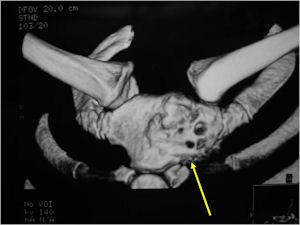

- There may be expansion of bone, cortical thinning and cortical breakthrough. A soft tissue mass may accompany this lesion but the soft tissue component is usually contained by the periosteum.

- The periosteum remains intact around the soft tissue component. Might need a CT scan to detect the subtle calcification (Egg Shell Rim of Calcification) associated with an intact periosteal reaction

- More useful for detecting mineralization and evaluating extent of bone destruction than plain X-ray

- Also useful in determining extent

- There is often extensive edema around the tumor in the surrounding bone and soft tissues that can lead to a misdiagnosis of a malignant tumor.